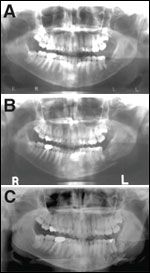

FIGURE 1

Osteonecrosis of the Jaw Presents as Exposed Necrotic Bone

Osteonecrosis of the jaw presents as exposed bone in the maxilla and/or mandible. The bone appears necrotic and nonvital. The surrounding mucosa is often inflamed due to secondary infection. Symptoms may range from mild to severe and include pain, drainage, swelling, and anesthesia/paresthesia. Although most case reports note a history of dentoalveolar surgical procedure prior to the development of ONJ (ie, dental extraction, dental implant placement, periodontal surgery, and endodontic surgical procedure), there are reports of patients who have developed ONJ spontaneously[8,11,12] (Figure 1).

FIGURE 2

Progressive Osteonecrosis of the Jaw May Lead to Pathologic Fracture

The radiographic findings in ONJ are variable. Less advanced ONJ or smaller areas of exposed bone (< 1 cm) is often undetectable on panoramic radiographs but shows faint signals or evidence of bony destruction on bone and CT/MRI scans. Progressive or advanced ONJ shows increased uptake on bone scans and "mottled bone" or areas of lytic changes on CT/MRI scans and panoramic radiographs (Figures 2 and 3).

FIGURE 3

Advanced Osteonecrosis of the Jaw